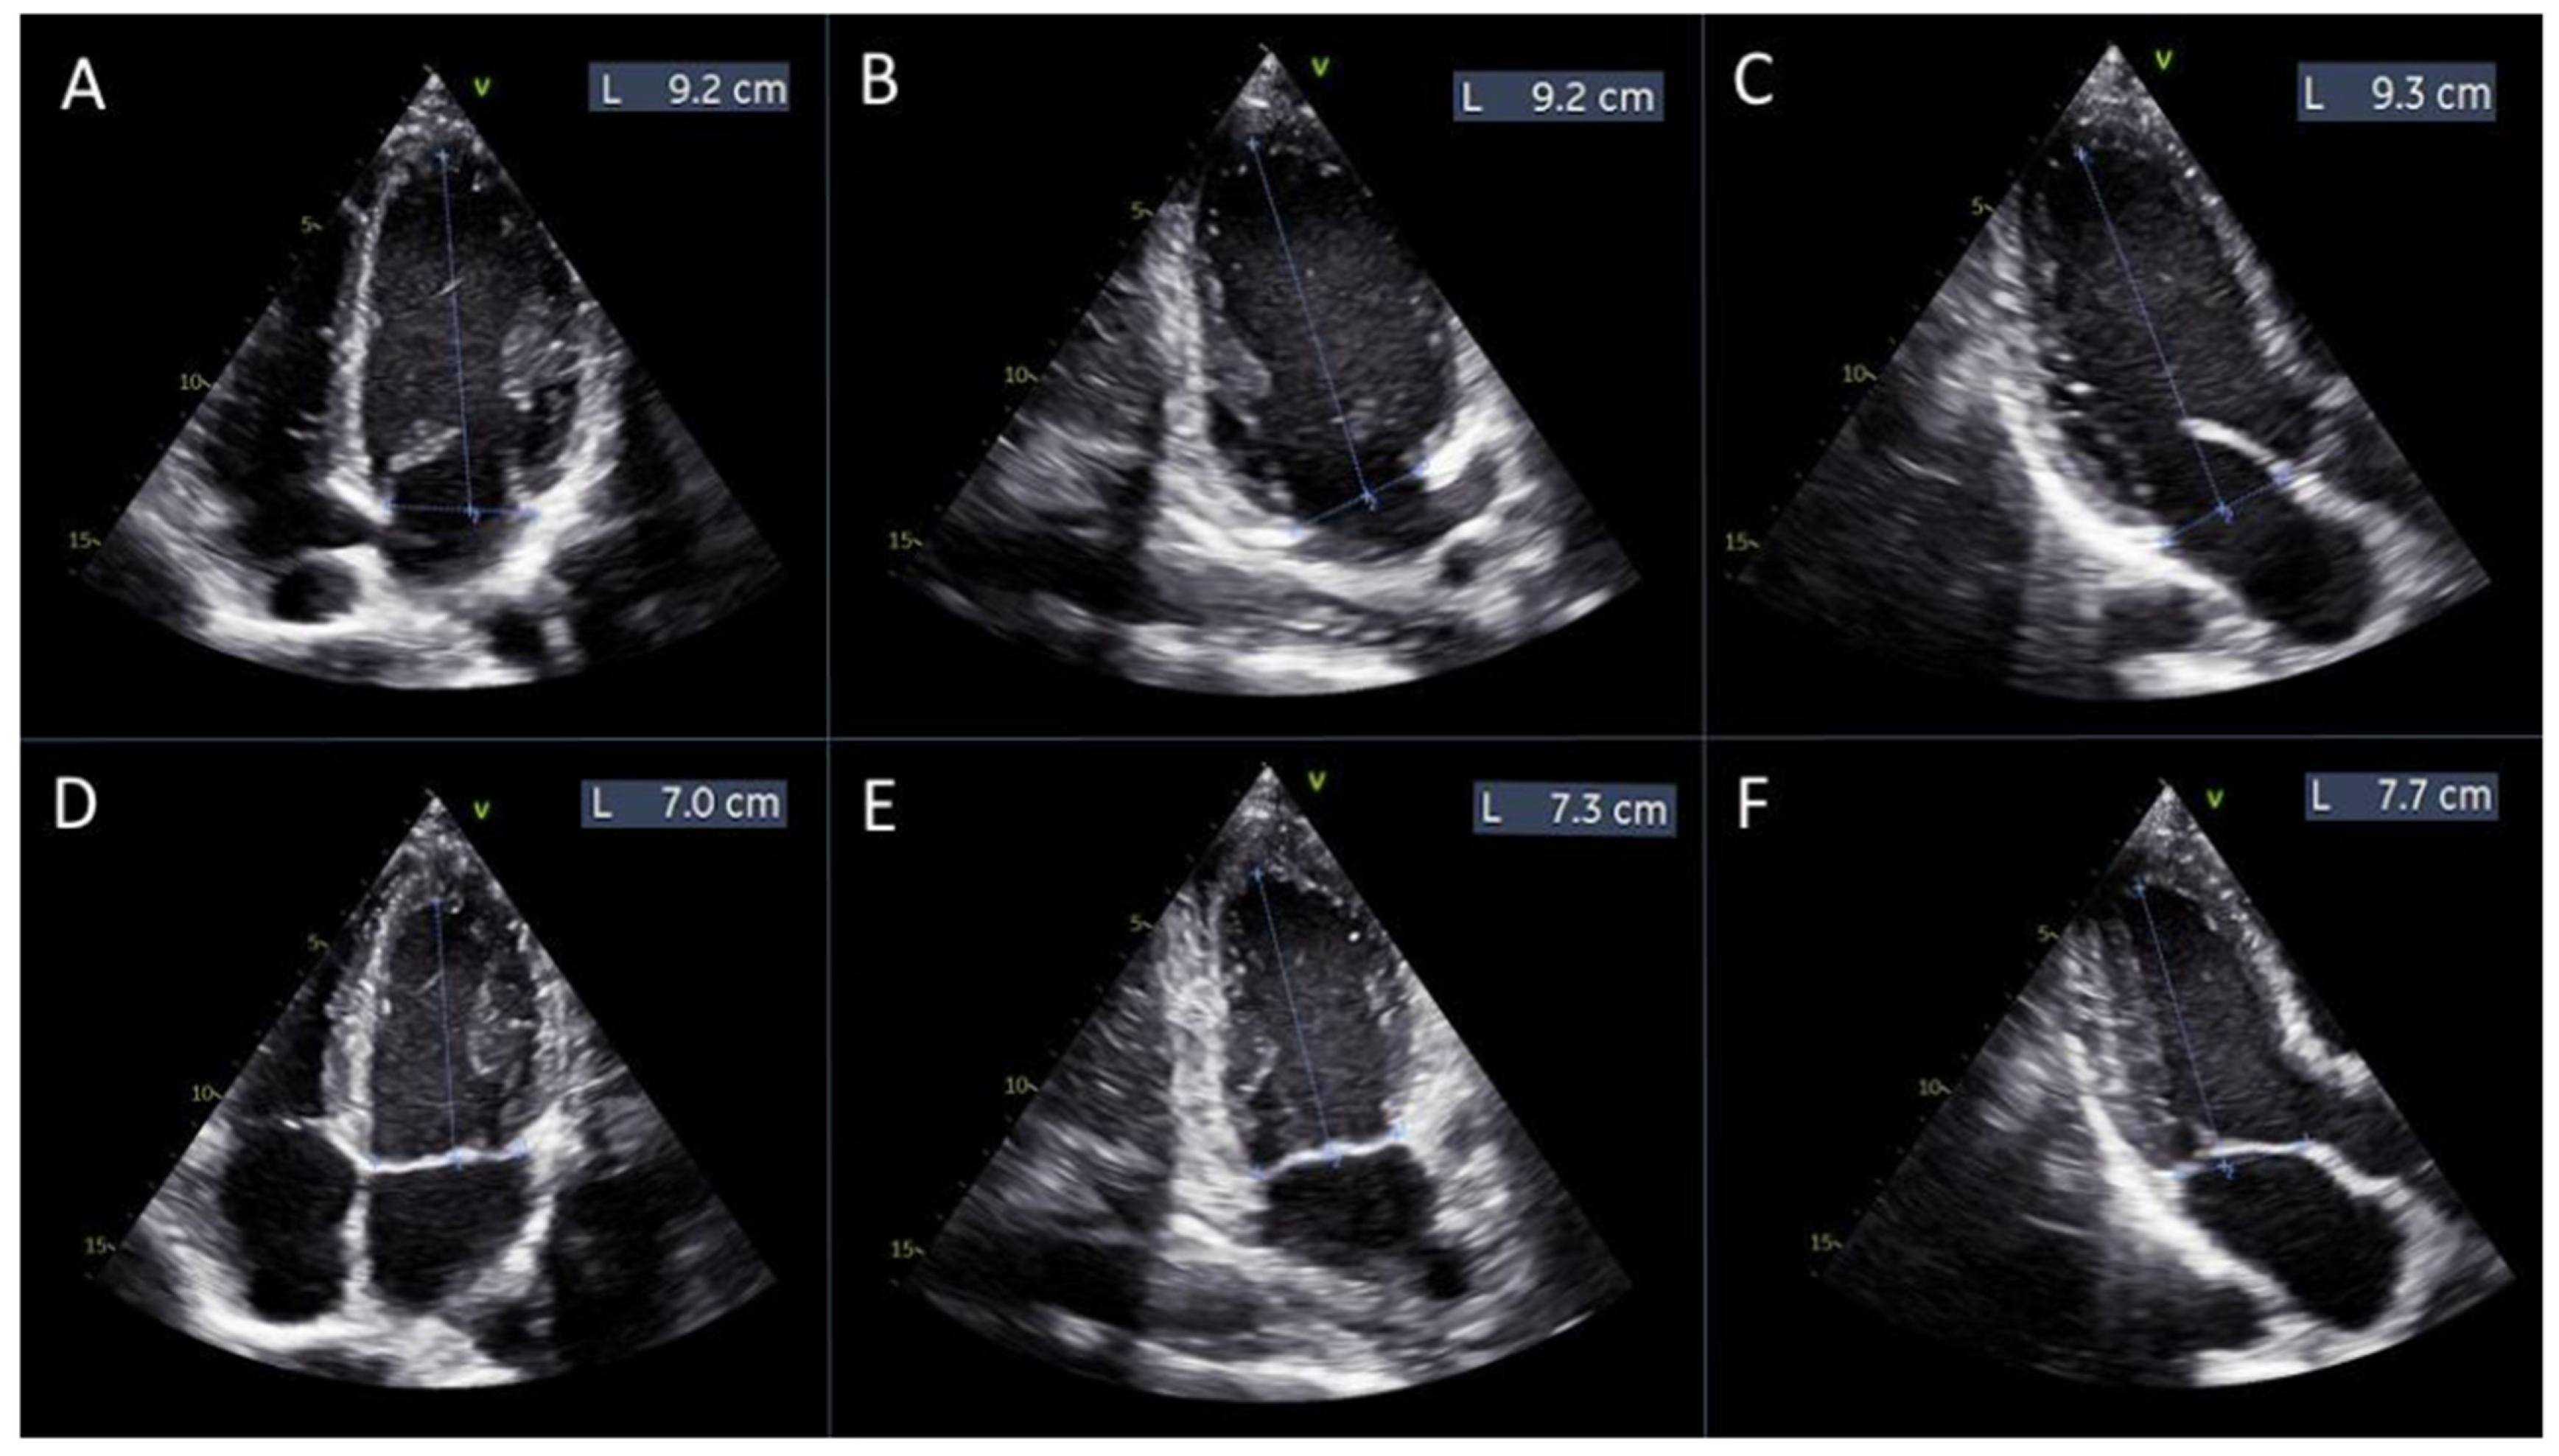

Based on the definitions of strain and displacement, we conducted manual measurements of the distances between the mitral annulus plane and the apex of the left ventricle at diastole and systole across all three apical views (4-chamber, 2-chamber, and 3-chamber).

Global left ventricular displacement was calculated as the difference in left ventricular length between diastole and systole, averaged across the three apical views. Subsequently, the average longitudinal displacement was divided by the average diastolic left ventricular length to derive the manual global longitudinal strain (GLSm), calculated using the following formula:

GLSm = (((L1d + L2d + L3d)/3) − ((L1s + L2s + L3s)/3))/((L1d + L2d + L3d)/3) × 100

where L1d, L2d, and L3d are the distances from the mitral annulus plane to the apex of the left ventricle in diastole, measured in the 4-chamber, 2-chamber, and 3-chamber views, respectively (Figure 2A–C).

L1s, L2s, and L3s are the distances from the mitral annulus plane to the apex of the left ventricle in systole, measured in the same views (Figure 2D–F).

Figure 2. Measurements of left ventricular length for manual global longitudinal strain calculation. Panels (AC) display the measurements of the left ventricular length obtained from the apical 4-chamber, 2-chamber, and 3-chamber views, respectively, at diastole. Panels (DF) show the corresponding measurements from the same apical views at systole.